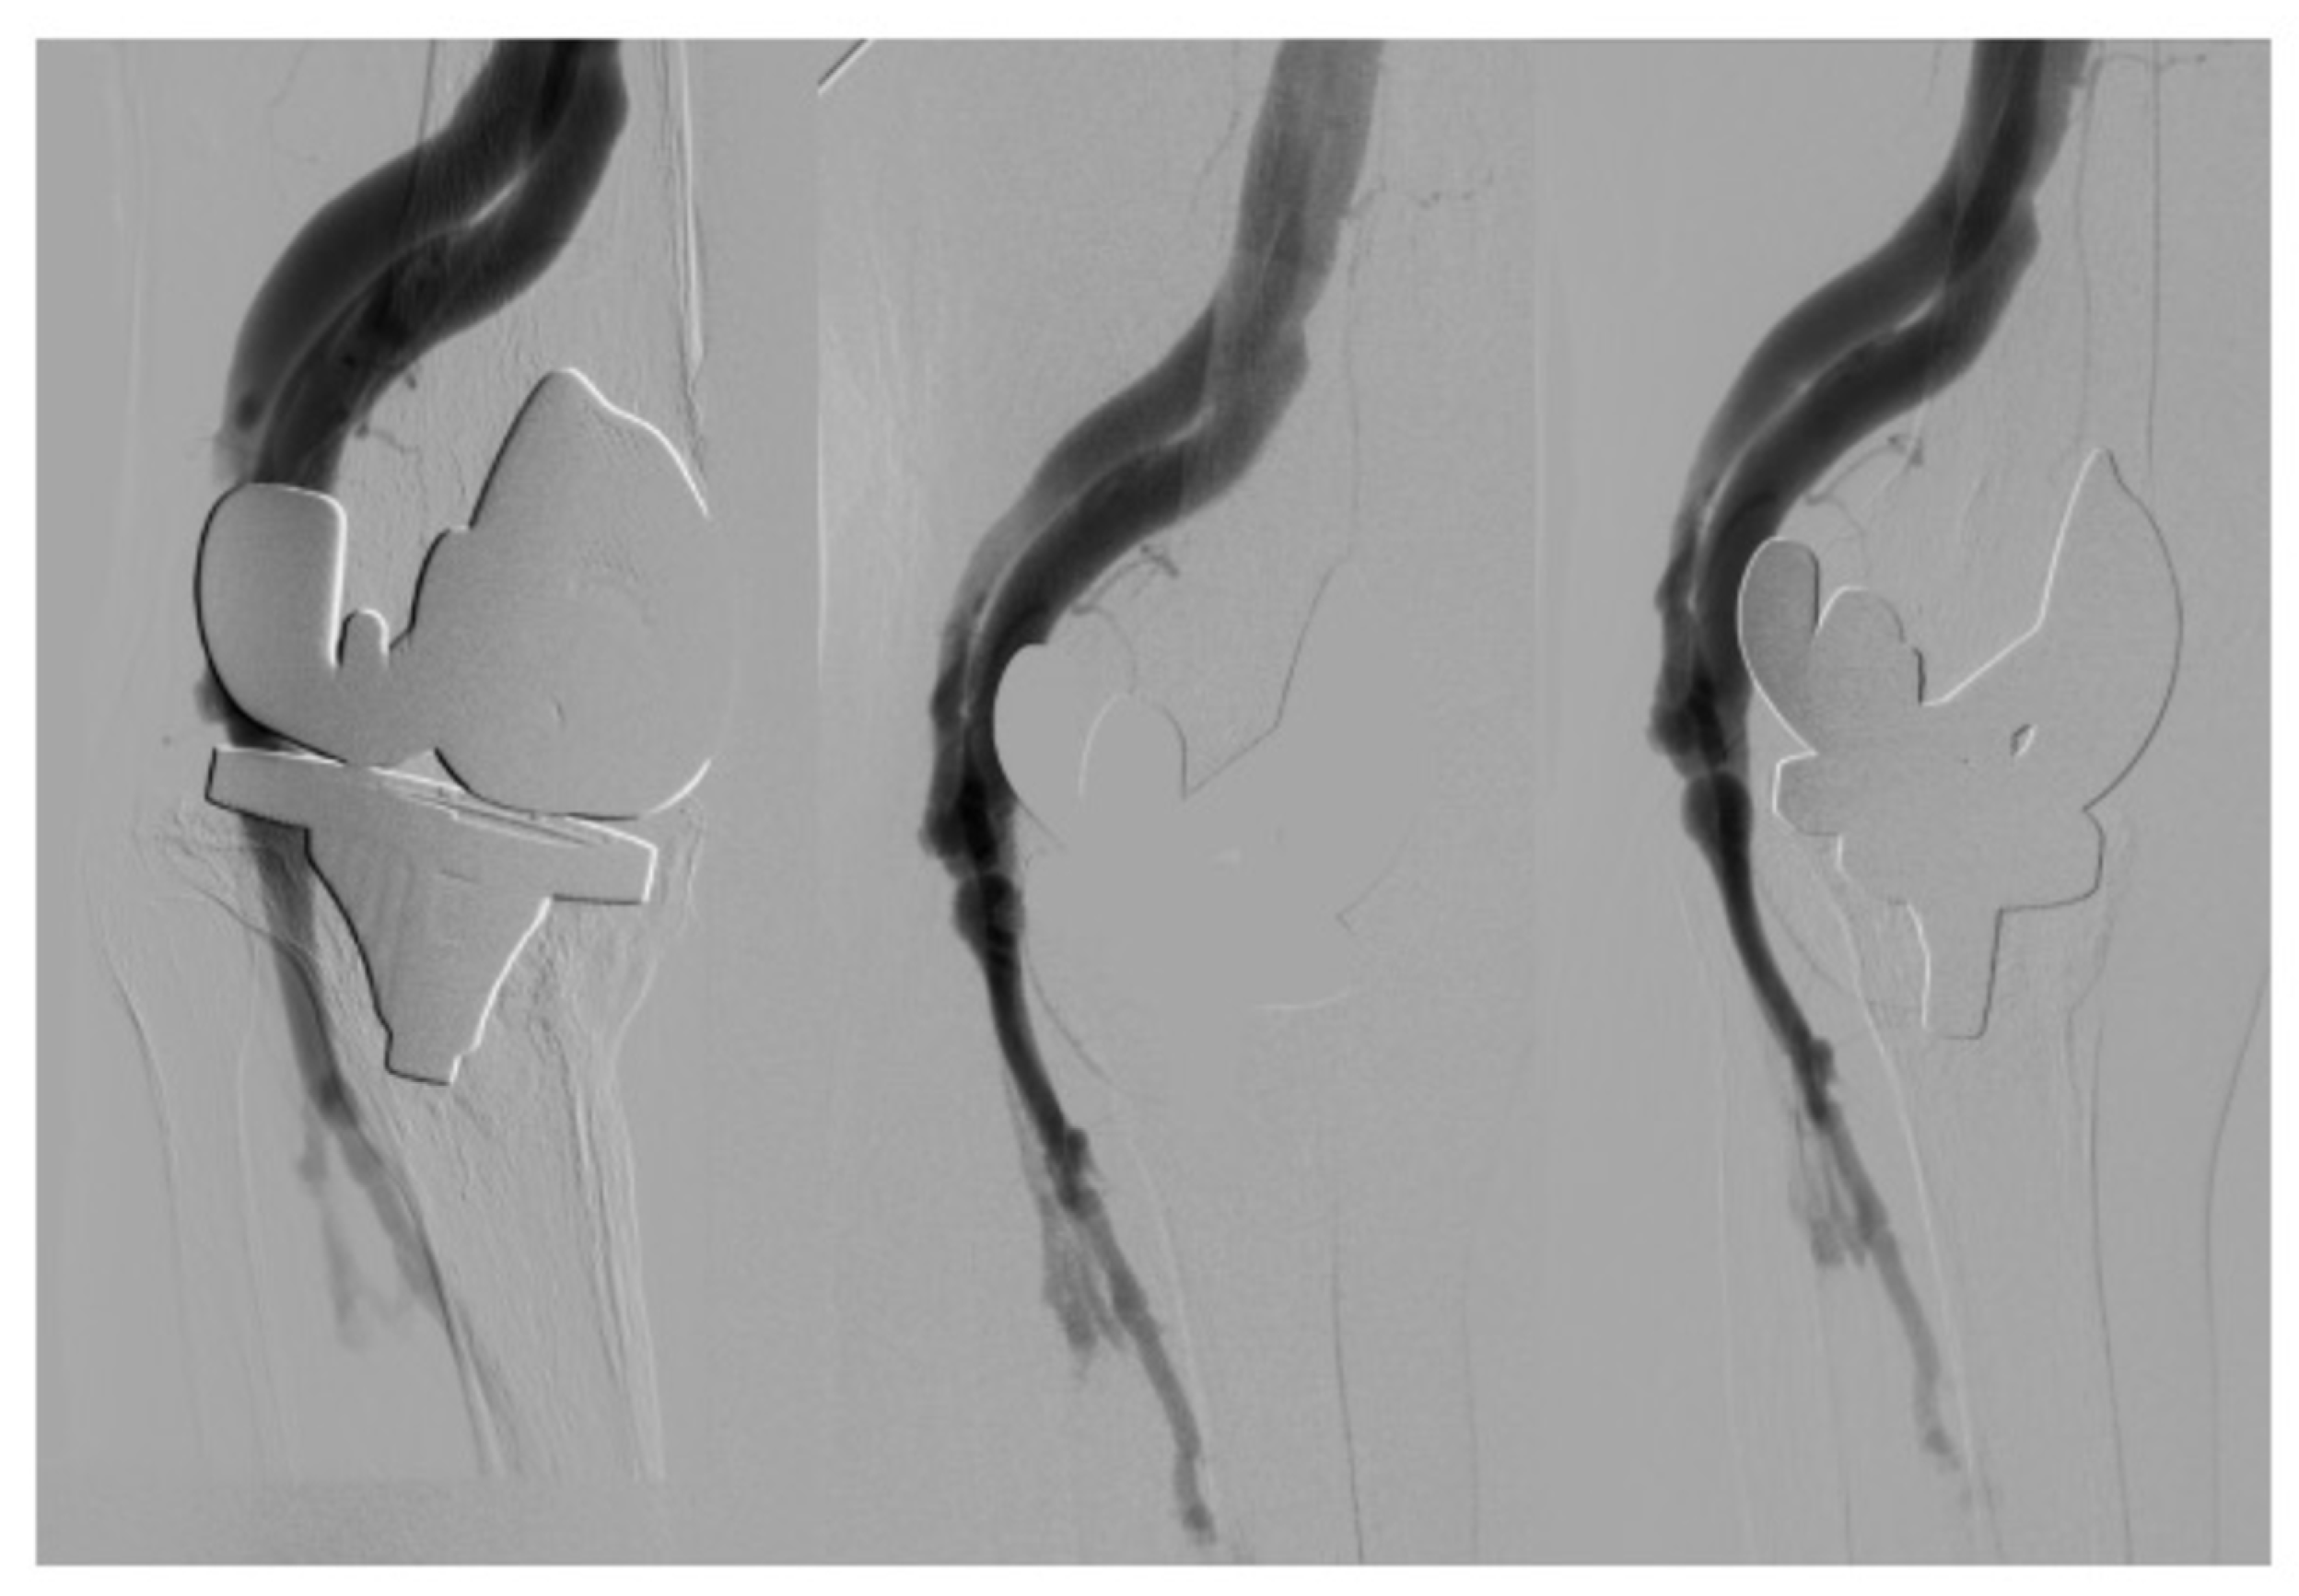

Informed of the therapeutic options (open and endovascular surgery), the patient chose an endovascular treatment, which was performed on 3 May 2013, with the successful insertion of a Viabahn® (WL Gore and Associates) (Figure 2).

Figure 2. Therapeutic arteriography: (A) check-up after inserting Viabahn® showing minimum packing of the vein sector; (B) Viabahn® at the level of popliteal artery; (C) final check-up after intra-stent angioplasty (absence of contrast passing to the vein sector).